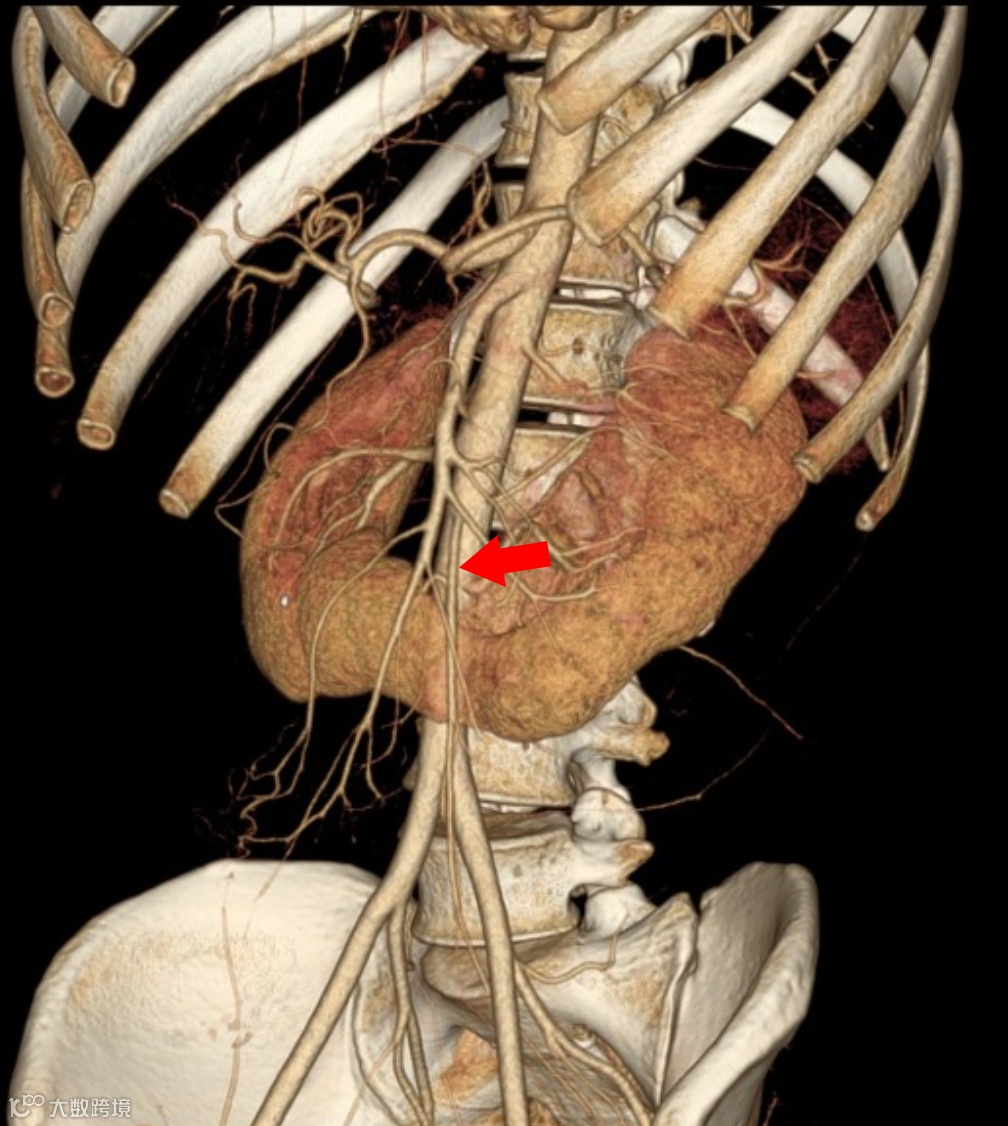

马蹄肾,双肾下极融合,峡部位于肠系膜下动脉(箭头)起始水平的下方。

连接双肾下极的肾实质或纤维组织峡部,跨过腹主动脉和下腔静脉前方,位于肠系膜下动脉起始水平的下方(这是马蹄肾位置低且无法上升到正常位置的关键原因,因为肠系膜下动脉像“钩子”一样挡住了它的上升通路)

可直接、三维地清晰显示双肾下极在中线处的实质融合。

位置与融合:两肾下极(90%)或上极(10%)在中线处融合,形成峡部,峡部多位于腹主动脉前方。

增强扫描:可清晰显示峡部血供来源,可能来自肾动脉、髂总动脉或肠系膜下动脉。

患者,男,60岁,因怀疑主动脉夹层而进行CTA检查,发现马蹄肾,肾峡部可见功能性肾实质,由三条肾动脉供血(箭头)。